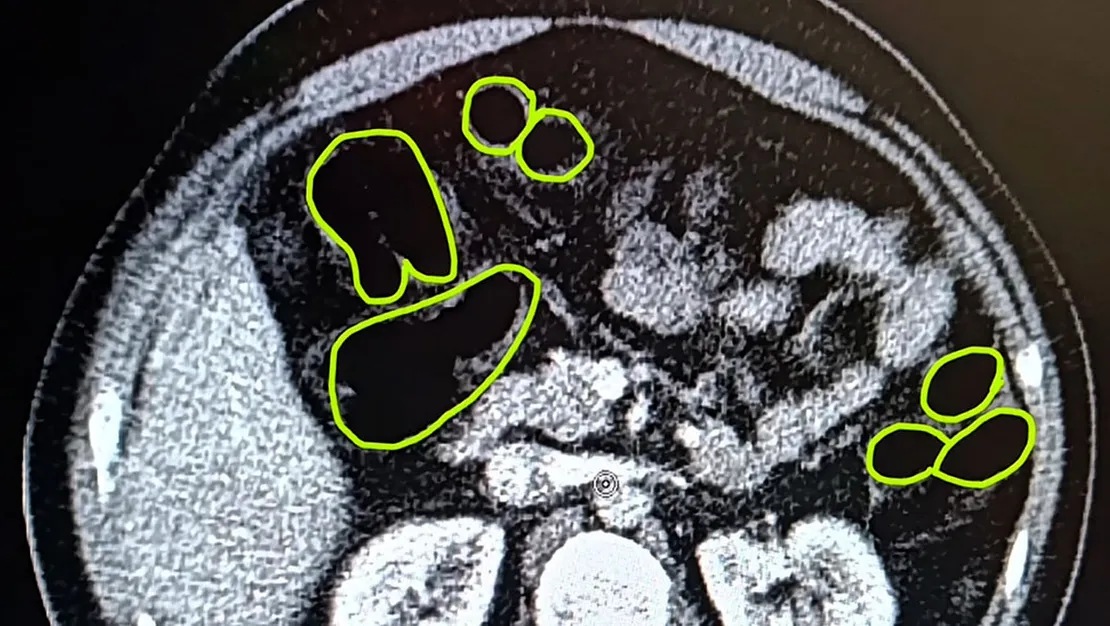

Gözaltına alınan 3 şüpheli, muayene edilmek üzere Kayseri Şehir Hastanesi’ne götürüldü. Burada gerçekleştirilen röntgen ve ultrason kontrollerinde, şüphelilerin midesinde uyuşturucu madde bulunduğu tespit edildi. Yuttukları uyuşturucuları kente sokmaya çalıştıkları belirlendi. Kapsüller, sağlık ekibinin müdahalesi ile çıkarıldı. Tedavi tamamlandıktan sonra şüpheliler, İlçe Jandarma Komutanlığı’na teslim edildi.